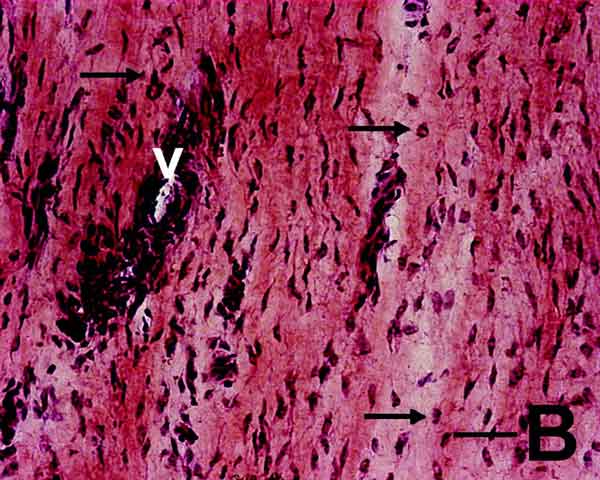

Tuttavia, ancora oggi, c’è molto da chiarire sul perché i tendini si ammalano. Considerando anche che il processo di guarigione di un tendine presenta delle difficoltà biologiche intrinseche.

L’obiettivo era stimolare i ricercatori a indagare meglio le relazioni tra le patologie metaboliche e le alterazioni della matrice extracellulare o delle cellule stesse in un tendine patologico. Le prime, spesso subcliniche, non sono facilmente diagnosticabili.

«Nonostante una serie di ipotesi, vi sono tuttora innumerevoli fattori totalmente sconosciuti che agiscono sui tendini; recentemente, si è parlato molto della genetica delle tendinopatie: non vi è dubbio che alcuni di noi hanno ereditato geni, o varianti di geni, che predispongono a tali affezioni – continua il prof. Maffulli, Presidente della Italian Society of Muscles, Ligaments and Tendons e responsabile medico delle ultime Olimpiadi di Londra – ma la grande prevalenza di malattie e disordini metabolici ci ha indotto, negli ultimi anni, a studiare le possibili connessioni fra problemi metabolici e malattie del Sistema muscoloscheletrico. Un nuovo orizzonte di ricerca si è aperto ai nostri occhi e abbiamo dimostrato come alterazioni subcliniche del metabolismo dei glicidi e dei lipidi si possano estrinsecare in affezioni tendinee».

«Inoltre – continua il dott. Oliva – studiando i tenociti umani in vitro, abbiamo riscontrato che, sotto stimolo degli ormoni tiroidei insieme con Vitamina C, queste cellule producono molto più collagene di tipo I rispetto ai controlli, che rappresenta la struttura proteica essenziale dei tendini sani. Queste ricerche potrebbero aprire nuove speranze di conoscenza delle patologie tendinee e nuove alternative terapeutiche».